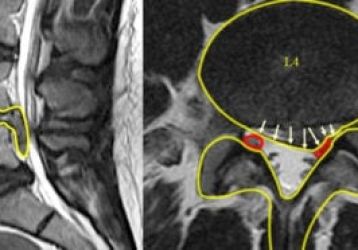

Что такое фораминальная грыжа межпозвонкового диска: симптомы, диагностика и лечение

Основные признаки фораминальной грыжи межпозвонкового диска, причины появления, симптомы, методы диагностики. Способы лечения, реабилитации и профилактики.